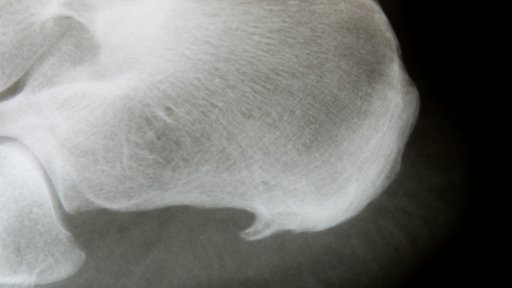

Schmerzen beim Laufen, Stehen und Gehen haben meist unterhalb der Ferse im Bereich der Fußsohle ihren Ursprung.

Jeder Schritt und auch das einfache Stehen werden bei einem Fersensporn und einer Plantarfasziitis, also dem Schmerz unter der Ferse, zur Qual. Besonders am Morgen, kurz nach dem Aufstehen, leiden Betroffene unter Belastungsschmerzen, die sich bis in die Zehen oder den Unterschenkel ziehen können.